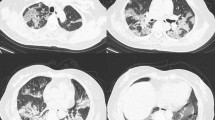

CT scan was performed within 1 day from admission. CT images were independently reviewed by two radiologists with 10 and 14 years of clinical experience: all radiologists were blinded to the clinical status of the patients. The lung parenchyma segmentation was performed through a software-based evaluation on a dedicated workstation using the open-source 3D Slicer software (Fig. 1). More details can be found in the Supplementary Information.

Quantitative CT analysis of a 74-year-old male COVID-19 patient. a Non-contrast chest CT on admission, showing a characteristic bilateral and subpleural ground glass opacity (GGO). b Well-aerated parenchyma segmented semi-automatically by a 3D slicer; the blue area is the result of the subtraction of the all parenchyma (HU − 1100; − 250) with GGO (− 700; − 250) + consolidation (− 250; + 150). c The GGO area, obtained by semi-automatic segmentation (HU − 700; − 250). d Manual segmentation of consolidation areas (HU − 250; + 150)